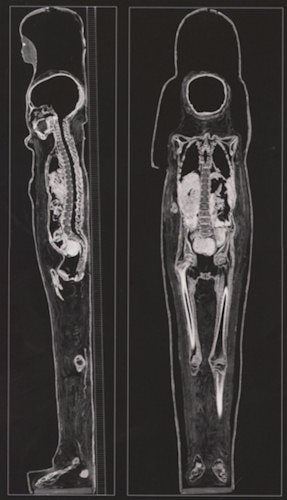

There is an exciting exhibition at the British Museum titled Ancient lives new discoveries: Eight mummies, eight stories. These eight mummies are examined using modern scanners and produce astonishing images. The older x-ray techniques have been replaced by the latest generation of dual-energy CT scanners. In a similar way to the older physical unwrapping, the modern CT scan can produce a virtual unwrapping, removing the various layers of the body down to the skeleton.

This reveals detailed biological information. The information was analyzed using methods developed by forensic archaeologists and physical anthropologists. Information about diet, the state of health, and the embalming techniques that were used are obtained. In the exhibition, the eight mummies are displayed with supporting material including the CT scan. The CT images are projected and can be virtually unwrapped and manipulated by the visitor using a touch-sensitive controller.

In the collection, two of the mummies are naturally mummified in the warm dry atmosphere of Egypt, and the other six are artificially embalmed. Considerable information can be obtained from the scans with information about age, lifestyle, and any diseases. In one of the mummies, calcific atheroma is clearly visibly as is poor dentition.

One of the advantages of radiology is that the internal contents of the mummy can be precisely determined. For example, on the outside, a bird mummy might contain a fish, and an apparently female mummy can be shown to be male.